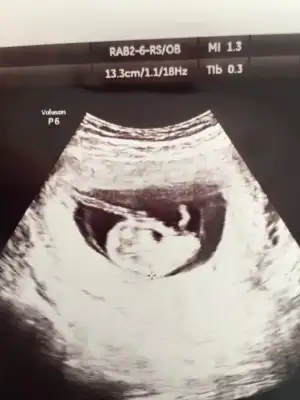

Bugün tam 12 haftalık görüntüsü doktor söylemedi cinsiyetini ikili teste gittim.Geçen hafta 11 haftalık ultrason görüntüsünü paylaşmıştım. Bu görüntülere göre yine bir tahmin bekliyorum 😁

Kız diyorum